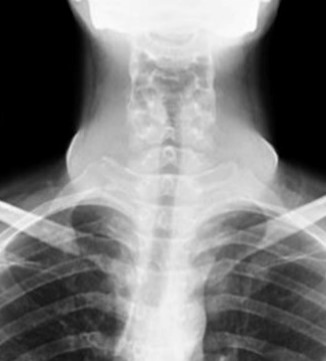

CT-Scan neck showed diffusely enlarged thyroid gland with heterogeneous enhancement but no calcification